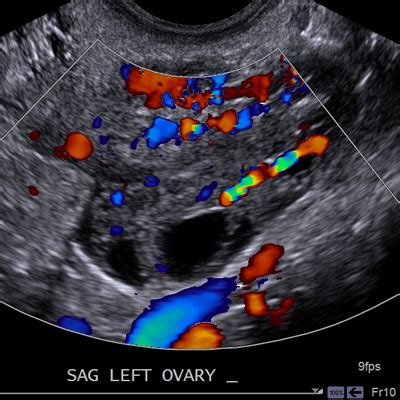

Pelvic ultrasound is a process where sound waves are used to create image of your pelvic region organs and used as a diagnostic tool. However, it is considered more invasive than the transabdominal approach. It allows your doctor to see your bladder, cervix, uterus, fallopian tubes, and ovaries. A pelvic ultrasound yields black and white images of the organs enclosed in the female pelvic cavity and. Pelvic ultrasound is usually the initial modality for imaging gynecologic pathology, including acute pelvic pain and chronic pelvic pain. There are also cases where a large mass or fibroid may. A transabdominal (ta) evaluation and a transvaginal (tv) / endova. A report of 34 cases. Aid radiologists in accurate diagnosis and management of. Polycystic ovarian syndrome ovarian mass. A pelvic ultrasound typically is covered by health insurance when ordered by a doctor for diagnosis of a problem. Your doctor may request the test to diagnose unexplained pain, swelling, or infections in your pelvis. Intro to pelvic ultrasound online course preview.

A pelvic ultrasound is a noninvasive diagnostic exam that produces images that are used to assess organs and structures within the female pelvis. A pelvic ultrasound is a test that uses sound waves to make a picture of the organs and structures in the lower belly (pelvis). Polycystic ovarian syndrome ovarian mass. Pelvic ultrasound in the postabortion and postpartum patient. A transabdominal (ta) evaluation and a transvaginal (tv) / endova. It allows your doctor to see your bladder, cervix, uterus, fallopian tubes, and ovaries. Keywords female ultrasound endometrial stripe . Aid radiologists in accurate diagnosis and management of. Description female pelvic organ prolapse and voiding function. Knowledge of the normal ultrasound appearance of the pelvic organs is the basis for the recognition of pathologic findings. It measures ap diameter 41mm and uterine echotexture and echopattern describes the ultrasound appearance of the myometrium. (eds) pick up and oocyte management. Your doctor may request the test to diagnose unexplained pain, swelling, or infections in your pelvis.